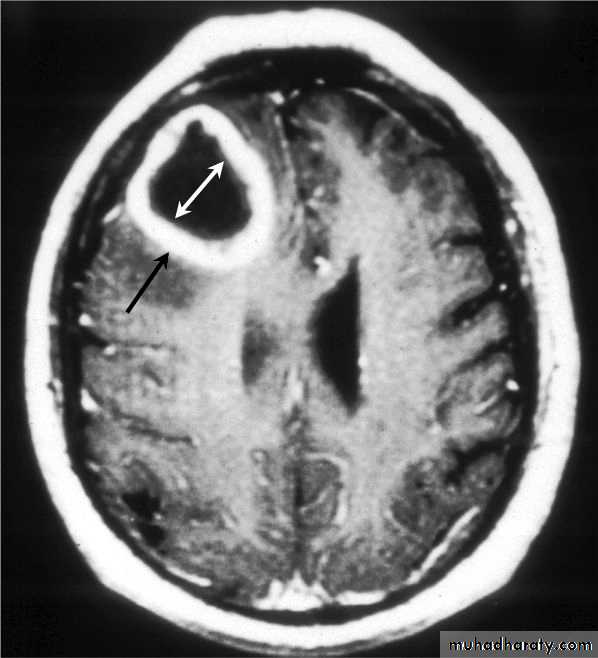

• B. Surgical treatment:• Indications for Excision (Craniotomy):

• Multilocular abscess.

• A superficial abscess.

• The presence of a foreign body.

• Fungal abscess.

• Cerebellar Abscesses.

• Abscesses containing air.

• Abscesses with CSF leak.

Multilocular Abscess

Superficial Abscess